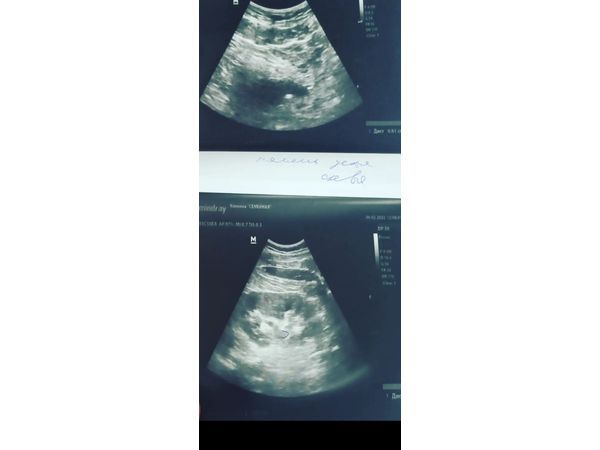

На верхнем снимке: камень в устье левого мочеточника; результаты нижнего снимка в пределах нормы